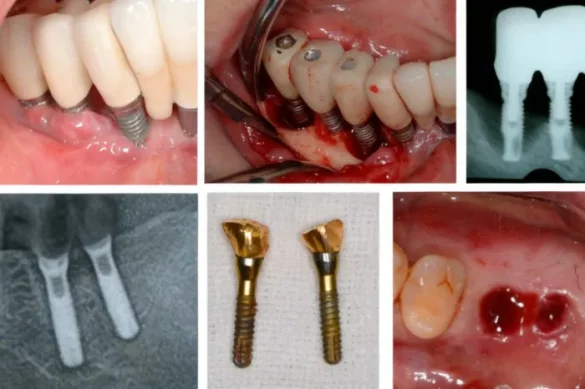

Removing a Failed Implant

Most failed implants need removal. Your dentist will numb the area with local anesthesia and may use a specialized tool to remove the implant with minimal damage to the surrounding bone. The jawbone contains few pain-sensing nerves, so the process is comfortable for most patients.

Treating the Site After Removal

After a failed implant is taken out, the dentist assesses the health of the remaining bone and soft tissues. If the bone is healthy and there is no infection, a new implant might be placed right away, but this is not always possible. Often, a bone graft is recommended to rebuild lost bone before a new implant is installed. Healing from a bone graft can take several months, and your dentist will monitor your progress.